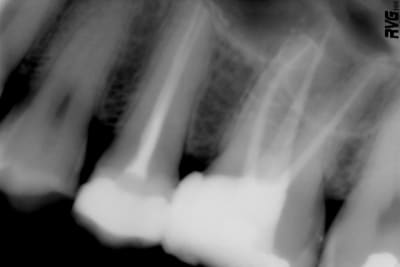

cette premiere molaire est asymptomatique.

que pensez-vous de cette endo ? satisfaisante ou non ?

faut il refaire le traitement endo avant de couronner la dent ?

nb : il n'y a aucun instrument fracturé

Elle est "radiologiquement jolie" mais si tu ne l'as pas faite toi même tu ne sais pas si la désinfection par la solution d'irrigation a été efficace.

8.5 sur 10 si tu veux quantifier radiologiquement.

Tous les dentistes aimeraient bien avoir cette moyenne satisfaisante à TOUTES leurs endos plutot que des ecarts type (echecs et parfois le super super rendu radio) AUTOUR de cette note!!!!

merci adhoc. Bien sur un jugemement a la seule vue de la radiographie ne peut etre exhaustif, mais cela reste un element determinant d'appreciation tout de même.

8,5 +0,5 pour la digue.